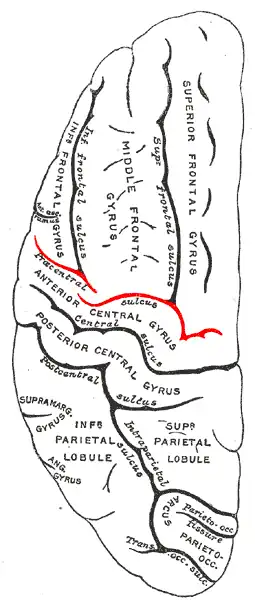

Lateral surface of left cerebral hemisphere, viewed from above. | |

Position of precentral sulcus (shown in red). -